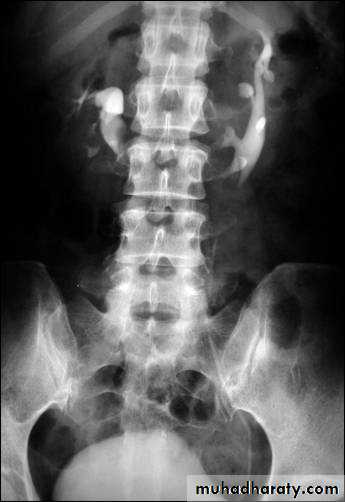

21- Horse shoe kidney